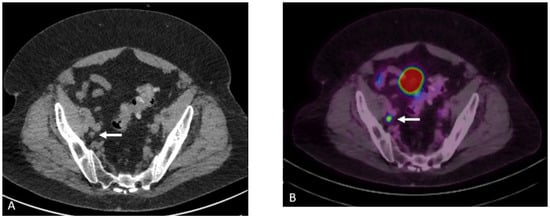

Detection of Loco-Regional Disease and Distant Metastases